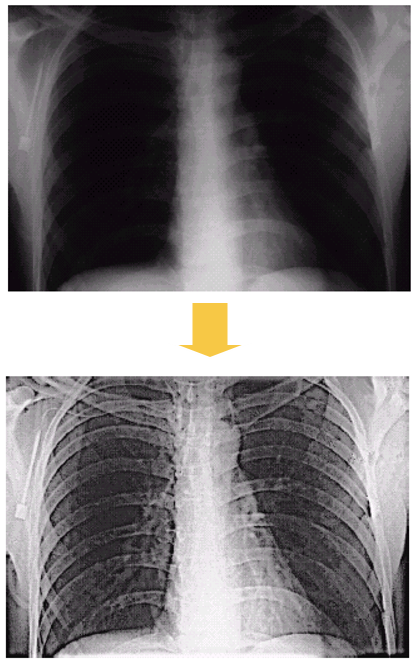

5.1 Image enhancement

Low-level: Image input $\rightarrow$ Image output

- Noise reduction

- Contrast enhancement

- Image sharpening